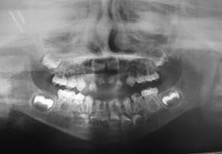

El examen clínico intraoral reveló alteración de la estructura y color de las piezas primarias, atrición y pérdida de la dimensión vertical (Figura 2). Radiográficamente se observó la presencia de coronas con marcada constricción cervical y raíces cortas (Figura 3). Presentaba alto riesgo cariogénico, por la presencia de lesiones de caries activas y dos restos radiculares, sumado a la anomalía estructural de la dentina (riesgo biológico específico) y bajo riesgo gingivoperiodontal. El riesgo socio-económico era alto por provenir de una familia con marcadas limitaciones económicas. Luego de la anamnesis, examen clínico y radiográfico, e interconsulta con el médico de cabecera se estableció el diagnóstico de DI Tipo I asociado a OI tipo I. Se planificó un tratamiento integral y preventivo con los objetivos de devolver forma y función, y proteger y evitar el desgaste de los tejidos conductas que pudieran interferir con el tratamiento.

Figura 3: Radiografía panorámica año 2007

En la radiografía panorámica de control del año 2015 se observó la progresiva obliteración del conducto radicular en el grupo incisivo superior e inferior y en los primeros molares permanentes; presentado los premolares en erupción, un conducto radicular anormalmente amplio en toda su longitud (Figura 8). En la del año 2018 se visualizó la continua aposición de dentina a nivel radicular que obliteró en forma casi total los conductos de la mayoría de las piezas dentarias, a excepción de los segundos molares inferiores (Figura 10).

Debido el alto porcentaje de abscesos periapicales, producto de la obliteración progresiva de los conductos radiculares, es fundamental el monitoreo radiográfico periódico en pacientes con DI.1 Los controles con radiografías panorámicas fueron realizados en el 2007, 2010, 2015 y 2018, sin registro de patologías pulpares periapicales.